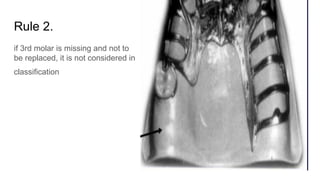

Rule 2.

if 3rd molar is missing and not to

be replaced, it is not considered in

classification